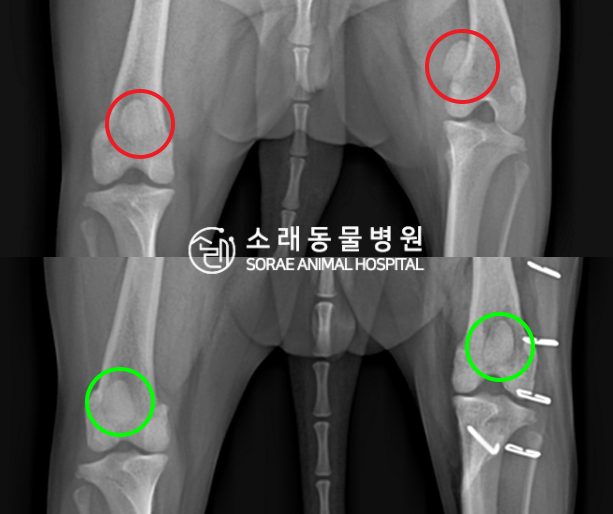

수술전과 수술후에 촬영한 푸이의 슬개골

방사선 사진입니다. 나란히 놓고 비교해보니

슬개골의 위치에 확연한 차이가 있는 것을

확인해 볼 수 있는데요. 내측으로 탈구되어 있던

슬개골이 원래 제자리인 활차구에 예쁘게

자리 잡고 있는 모습을 확인할 수 있었습니다.